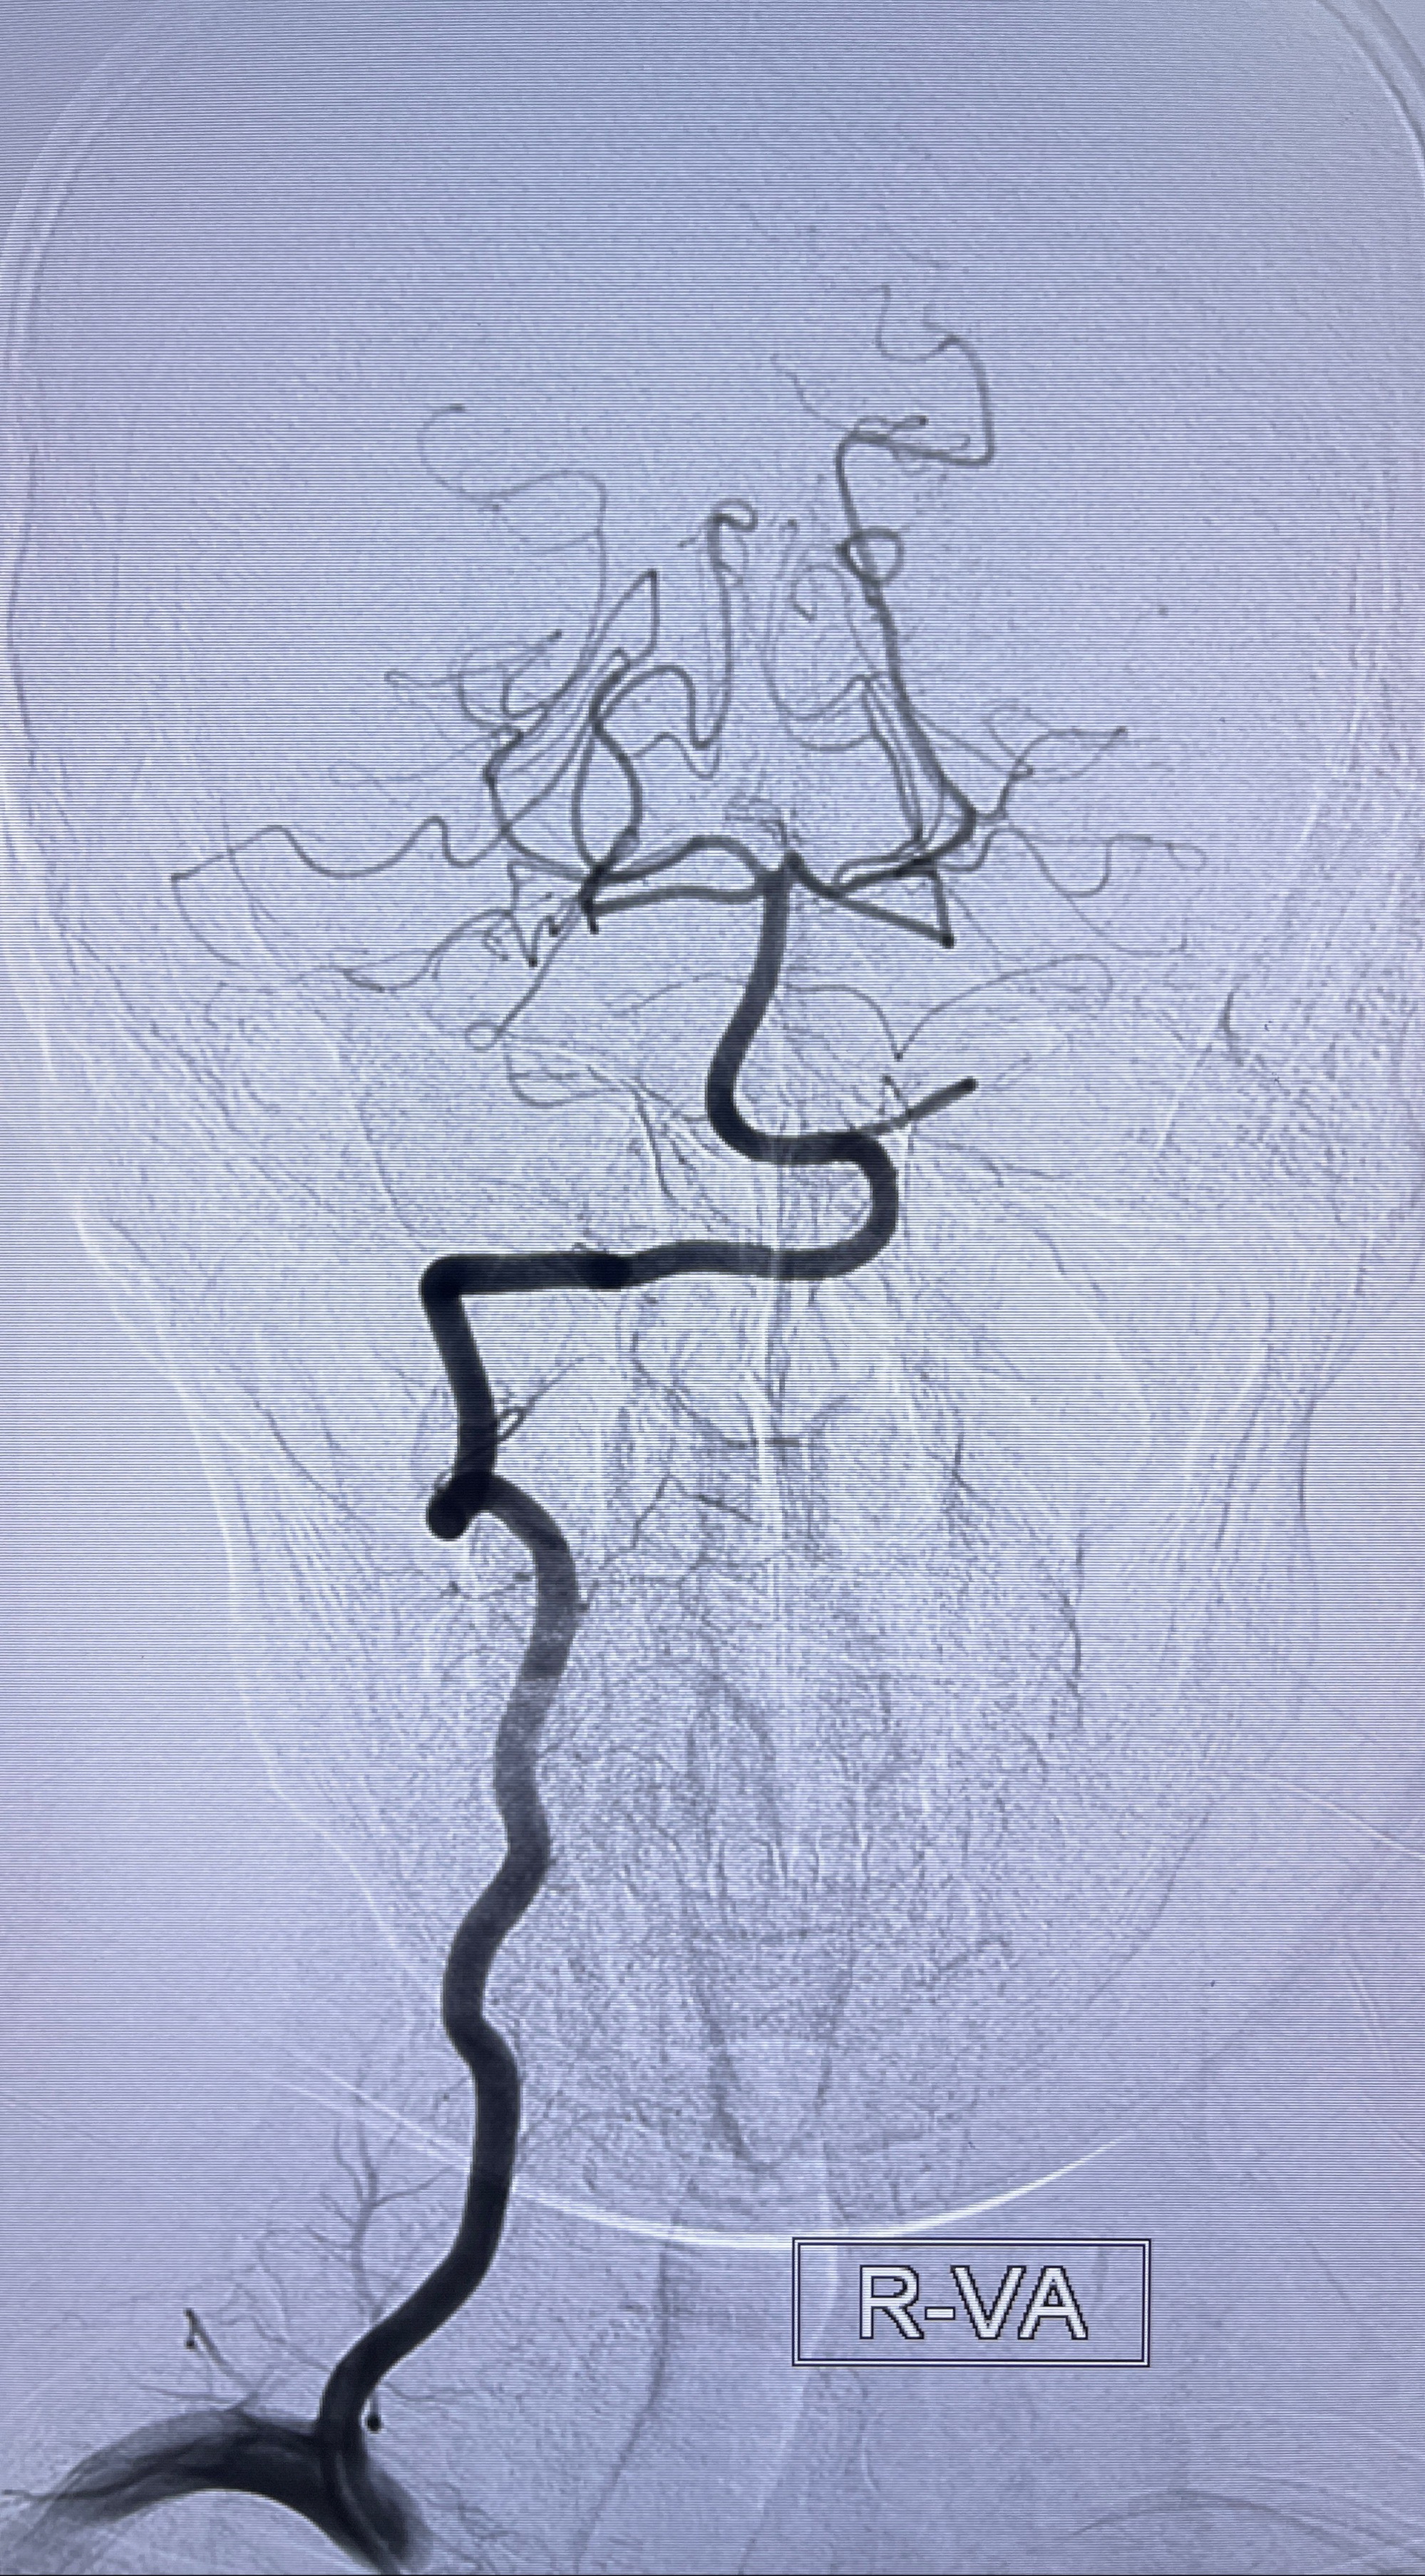

2023年8月21日]景德镇市第一人民医院脑血管造影检查,提示:主动脉弓、双侧颈总动脉、锁骨下动脉造影未见异常,左侧大脑前动脉静脉瘘。

2023-09-13全脑血管造影:前颅底硬脑膜动静脉瘘,供血动脉为双侧胼周动脉、眼动脉脑膜支,静脉向上矢状窦方向引流